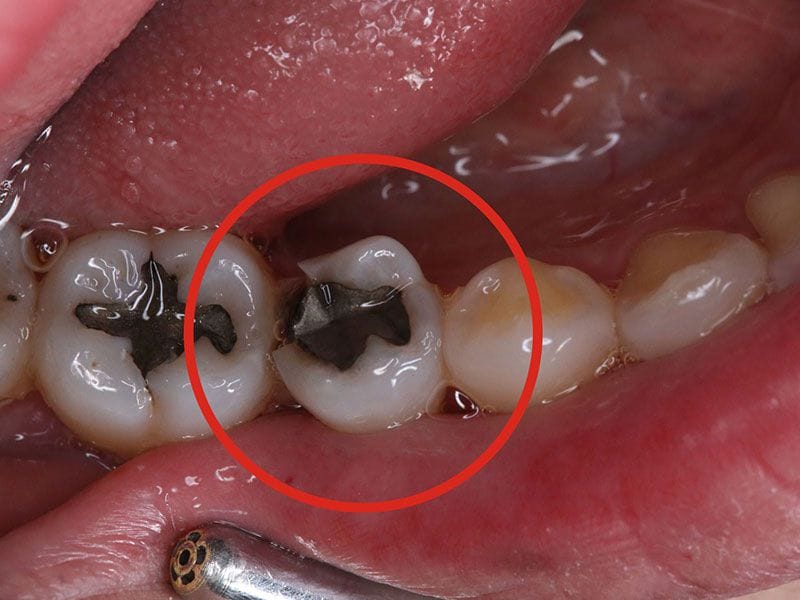

除汞中

首先要用高速鑽針將原有的銀粉移除,除汞過程最重要的就是避免吸入鑽下來的碎屑及因高溫產生的汞蒸汽,所以我們會用橡皮障隔離口腔,加上高速抽吸裝置吸走汞蒸汽。